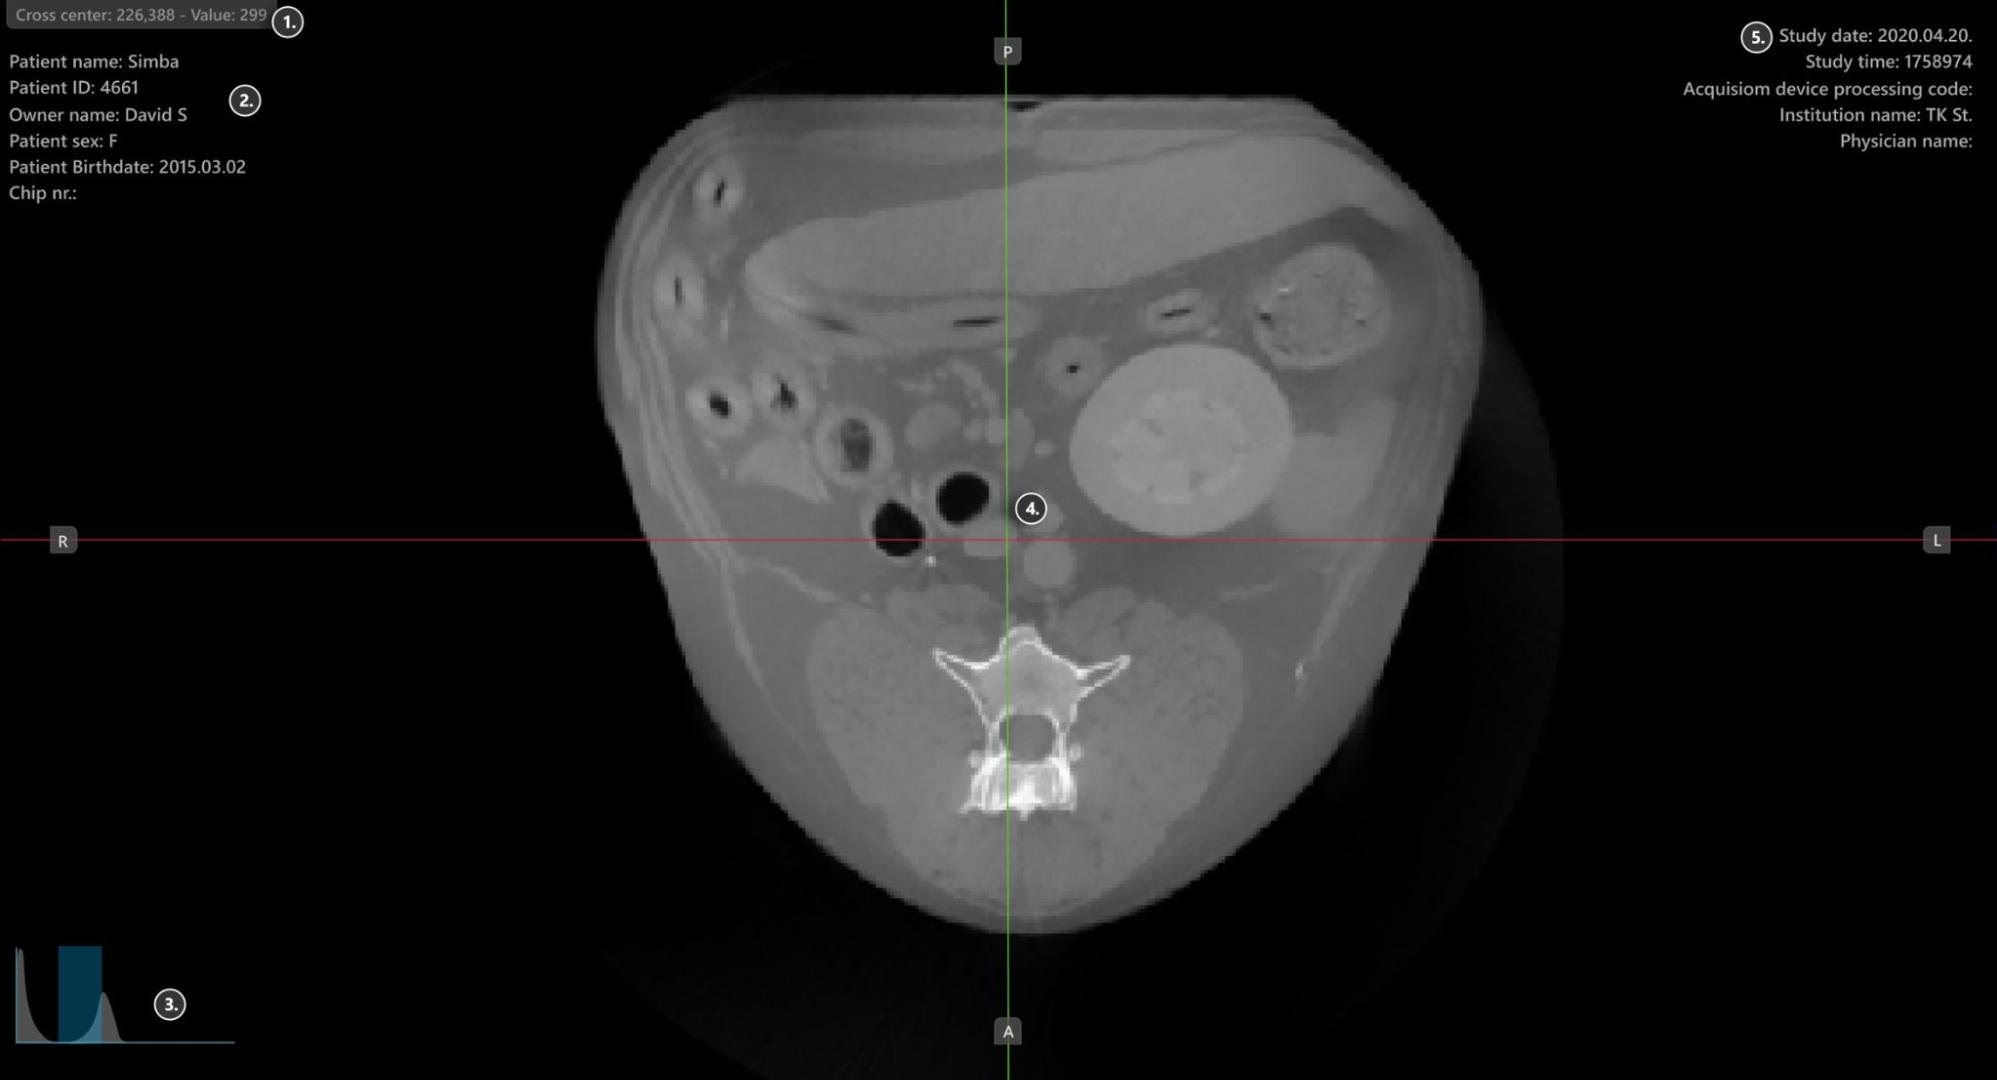

Viewer-Bereich¶

HU (Hounsfield-Einheit) Pixelwert

Patienteninformationen

Histogramm-Werkzeug für Windowing

Slicer

Studieninformationen